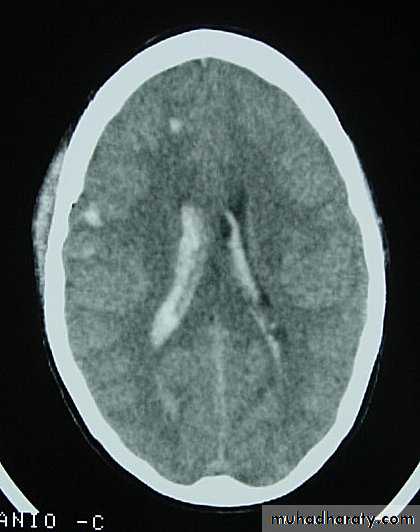

c. Intracerebral Haematoma

This is the least common of traumatic haematoma.

They are due to areas of traumatic contusion coalescing into a contusional haematoma.

Disrupted cerebral tissue release thromboplastins that potentiate haemorrhage.

CT scan: appear as hyperdence lesions with associated mass effect and midline shift.

Large intracerebral haematomas should be evacuated unless the patient’s neurological state is improving.

Small inracerebral haematomas may not require removal, but be aware that they can expand.